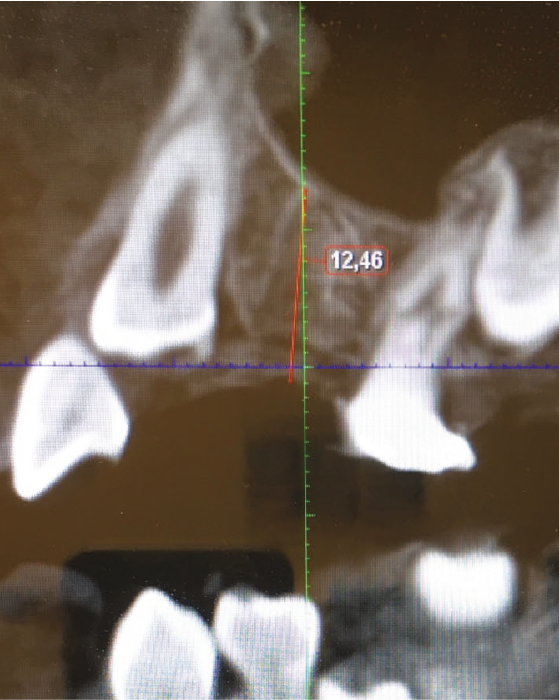

Un bilan radiologique 3D (Cone Beam CT) est prescrit dans le but d’évaluer, avec l’équipe de chirurgie du Dr Jean-Luc Charrier (Hôpital Bretonneau), la possibilité de transplantation d’une prémolaire du secteur 4 vers le secteur 1 et de définir le meilleur transplant possible entre 44 et 45. Sont analysées les dimensions du site receveur ainsi que l’anatomie, la position et l’état de maturation radiculaire des prémolaires candidates à la transplantation (fig. 3).

Cet examen nous apprend que :

- concernant le site receveur : son volume osseux est suffisant pour accueillir une des prémolaires du secteur 4 ;